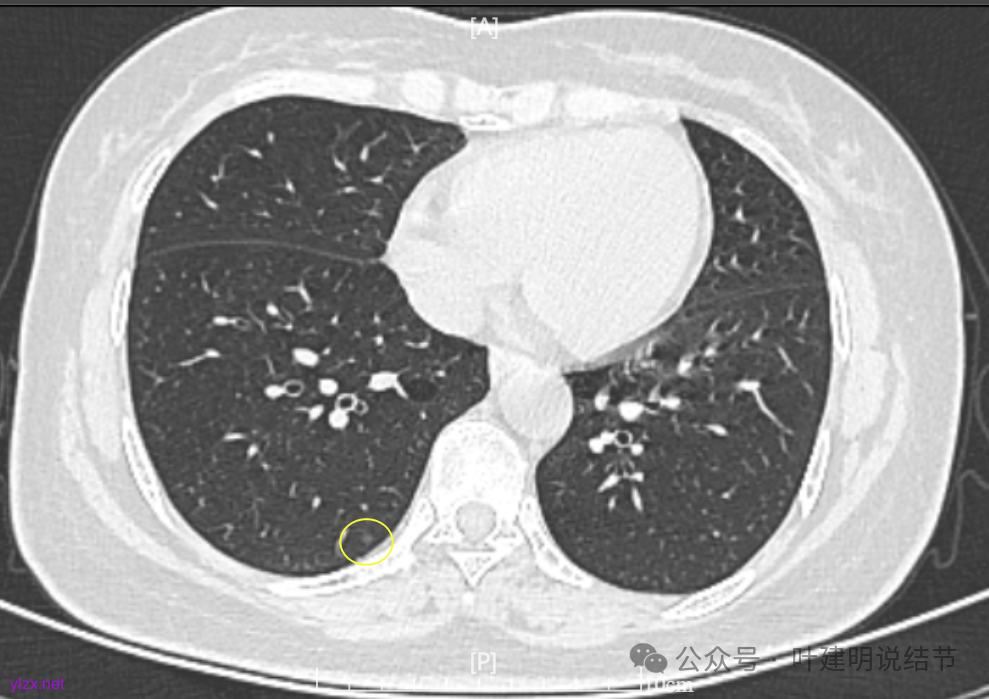

病灶7:右下叶胸膜下淡而微小的磨玻璃结节,考虑肺泡上皮增生可能性大。

两肺多发结节,持续存在,总体上看,瘤肺边界清,轮廓清楚,主病灶有血管穿行,表面也不平,考虑微浸润性腺癌可能性大,其他2处不典型增生或原位癌可能性大些。总的来说,风险还不大,也不会引起胸痛症状,但因两侧都有,且可能后续均是要手术的,个人觉得左侧病灶可以考虑先切除,因为两个病灶离得不远,总的来说还是靠边缘的,定位后楔形切除能将两处都切了。这样只需再关注右侧的,以后真右侧也要手术,也可拉长两次手术的间隔时间,有利于恢复以及耐受性会好些。两侧同时手术,疼痛、咳嗽、恢复情况容易差些,也容易合并肺炎或其他并发症,安全性差一点的。以上意见供参考!